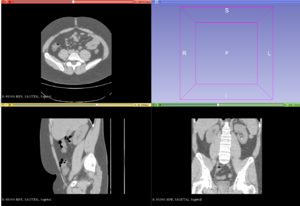

Publication: PLoS One. 2018 Aug 16;13(8):e0202387. PMID: 30114235 | PDF Authors: Reynolds HM, Parameswaran BK, Finnegan ME, Roettger D, Lau E, Kron T, Shaw M, Chander S, Siva S. Institution: Department of Physical Sciences, Peter MacCallum Cancer Centre, Melbourne, Victoria, Australia. Abstract: PURPOSE: To explore the utility of diffusion and perfusion changes in primary renal cell carcinoma (RCC) after stereotactic ablative body radiotherapy (SABR) as an early biomarker of treatment response, using diffusion weighted (DWI) and dynamic contrast enhanced (DCE) MRI. METHODS: Patients enrolled in a prospective pilot clinical trial received SABR for primary RCC, and had DWI and DCE MRI scheduled at baseline, 14 days and 70 days after SABR. Tumours <5cm diameter received a single fraction of 26 Gy and larger tumours received three fractions of 14 Gy. Apparent diffusion coefficient (ADC) maps were computed from DWI data and parametric and pharmacokinetic maps were fitted to the DCE data. Tumour volumes were contoured and statistics extracted. Spearman's rank correlation coefficients were computed between MRI parameter changes versus the percentage tumour volume change from CT at 6, 12 and 24 months and the last follow-up relative to baseline CT. RESULTS: Twelve patients were eligible for DWI analysis, and a subset of ten patients for DCE MRI analysis. DCE MRI from the second follow-up MRI scan showed correlations between the change in percentage voxels with washout contrast enhancement behaviour and the change in tumour volume (ρ = 0.84, p = 0.004 at 12 month CT, ρ = 0.81, p = 0.02 at 24 month CT, and ρ = 0.89, p = 0.001 at last follow-up CT). The change in mean initial rate of enhancement and mean Ktrans at the second follow-up MRI scan were positively correlated with percent tumour volume change at the 12 month CT onwards (ρ = 0.65, p = 0.05 and ρ = 0.66, p = 0.04 at 12 month CT respectively). Changes in ADC kurtosis from histogram analysis at the first follow-up MRI scan also showed positive correlations with the percentage tumour volume change (ρ = 0.66, p = 0.02 at 12 month CT, ρ = 0.69, p = 0.02 at last follow-up CT), but these results are possibly confounded by inflammation. CONCLUSION: DWI and DCE MRI parameters show potential as early response biomarkers after SABR for primary RCC. Further prospective validation using larger patient cohorts is warranted. |

Baseline ADC map with tumour contour in red for patient 3 and associated histogram showing the frequency of ADC values in each MRI scan. ADC maps were read into 3D Slicer software and the tumour volume contoured directly onto ADC map image slices by an experienced radiologist. |